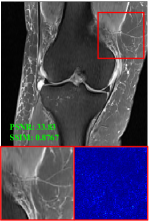

4.3 Qualitative results

Figure 5 provides the qualitative comparison of the various methods on the four datasets at a scale of 4. The top, second, third, and bottom rows are the SR results under the FastMRI, clinical brain, clinical tumor and clinical pelvic datasets, respectively. The red boxes indicate the zoom-in region of complicated anatomical structures along with their corresponding error maps. Note that the brighter textures in the error maps, the lower the quality of the reconstructed images. As can be seen, compared to methods based on Transformers and CNNs, diffusion-based methods like DisC-Diff and DiffMSR (Ours) are capable of reconstructing high-realistic images with promising reconstruction metric scores (PSNR and SSIM). Nevertheless, while DisC-Diff can reconstruct high-precision MR images, it does not preserve the structure present in the original HR images, introducing some additional information that can affect medical diagnosis. In contrast, our method combines DM and PLWformer, which can preserve the original image’s structure while restoring high-frequency information.

9 More Visual Comparisons

In this section, we present more visual qualitative comparisons. Figures 8, 9, 10, and 11 show the reconstruction results of each method in FastMRI, clinical brain, clinical tumor, and clinical pelvic, respectively. As can be seen, although DisC-Diff can reconstruct MR images with high-frequency information, it fails to preserve the structure and content of the original Target HR image effectively, resulting in image distortion. In contrast, our proposed DiffMSR can restore high-frequency information while preserving the structure of the original HR image, indicating the effectiveness of the joint use of DM and PLWformer.